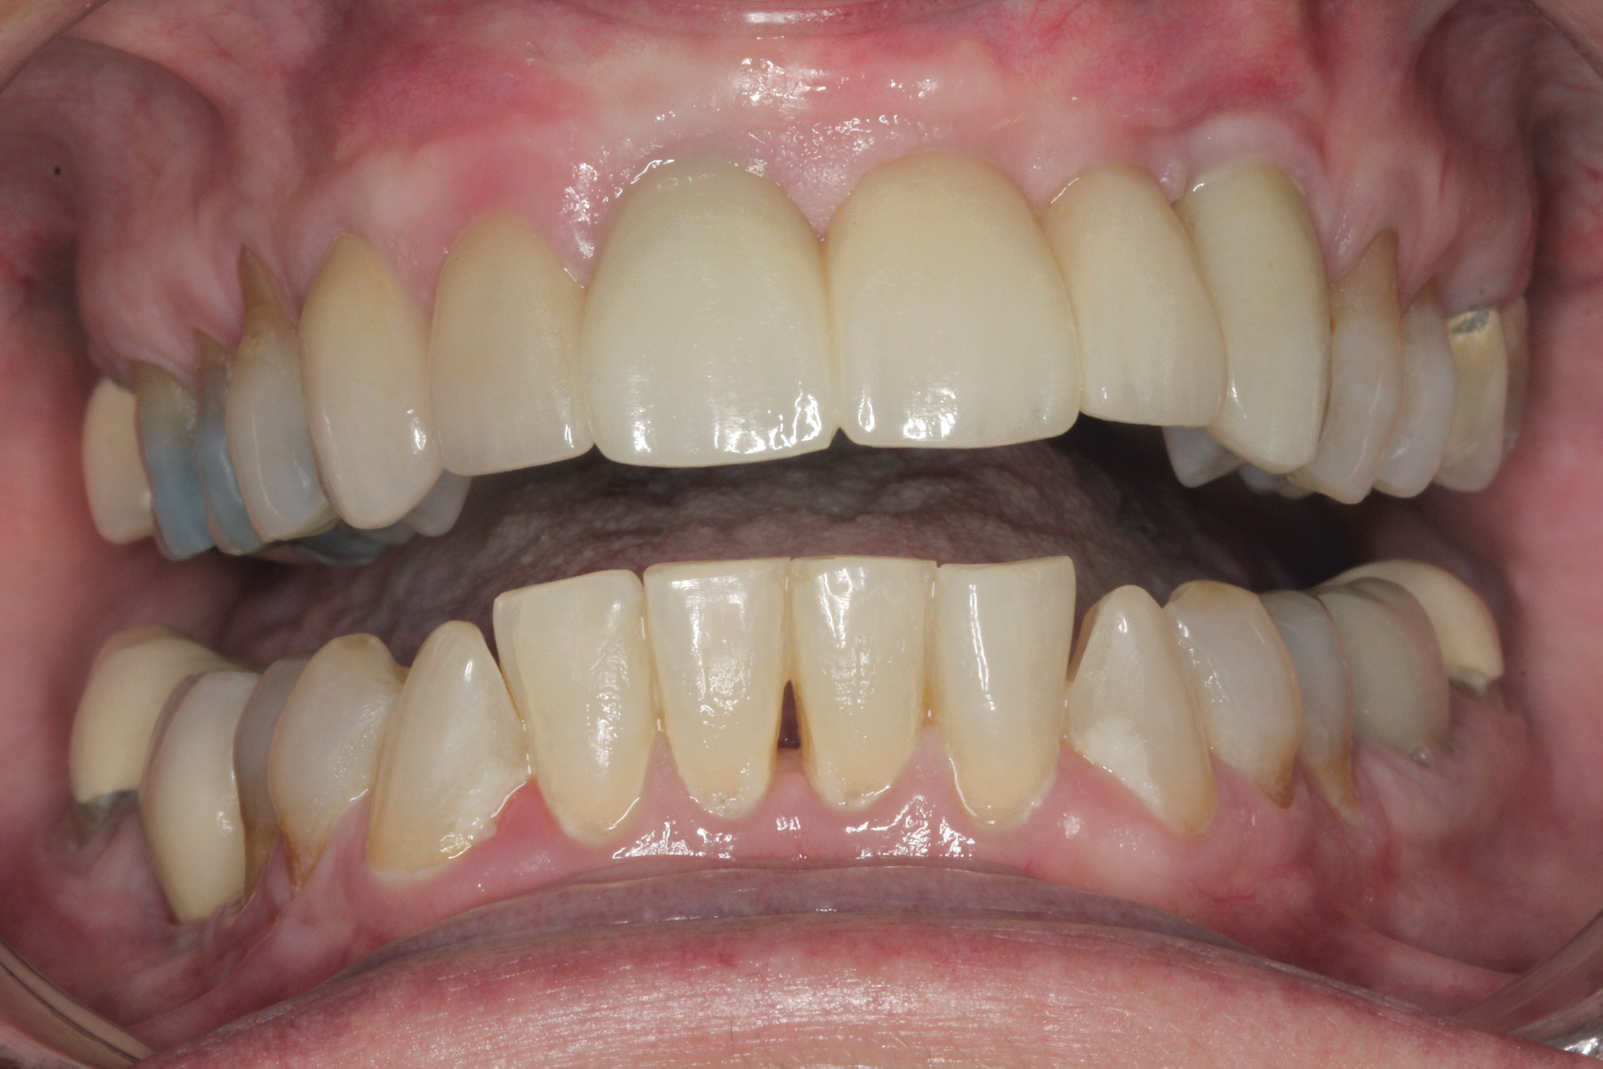

Fig 7. Seibert Class I defect in teeth Nos. 10 and 11 with Miller Class I to II recession on multiple teeth (Fig 7). A tuberosity CTG was used to treat the edentulous area at Nos. 10 and 11 and the periodontal recession on teeth Nos. 7 and 9. Allograft material was used to treat the other areas of periodontal recession. The final esthetic restorative treatment was completed with crowns on all upper teeth except for a bridge from Nos. 8 through 12 with ovate pontics in Nos. 10 and 11 (Fig 8). Note a keloid-like appearance was evident over teeth Nos. 7 and 9 due to ineffective trimming of the grafts (restorative treatment completed by Todd D. Gruen, DDS).

Figure 7

Fig 8. Seibert Class I defect in teeth Nos. 10 and 11 with Miller Class I to II recession on multiple teeth (Fig 7). A tuberosity CTG was used to treat the edentulous area at Nos. 10 and 11 and the periodontal recession on teeth Nos. 7 and 9. Allograft material was used to treat the other areas of periodontal recession. The final esthetic restorative treatment was completed with crowns on all upper teeth except for a bridge from Nos. 8 through 12 with ovate pontics in Nos. 10 and 11 (Fig 8). Note a keloid-like appearance was evident over teeth Nos. 7 and 9 due to ineffective trimming of the grafts (restorative treatment completed by Todd D. Gruen, DDS).

Figure 8